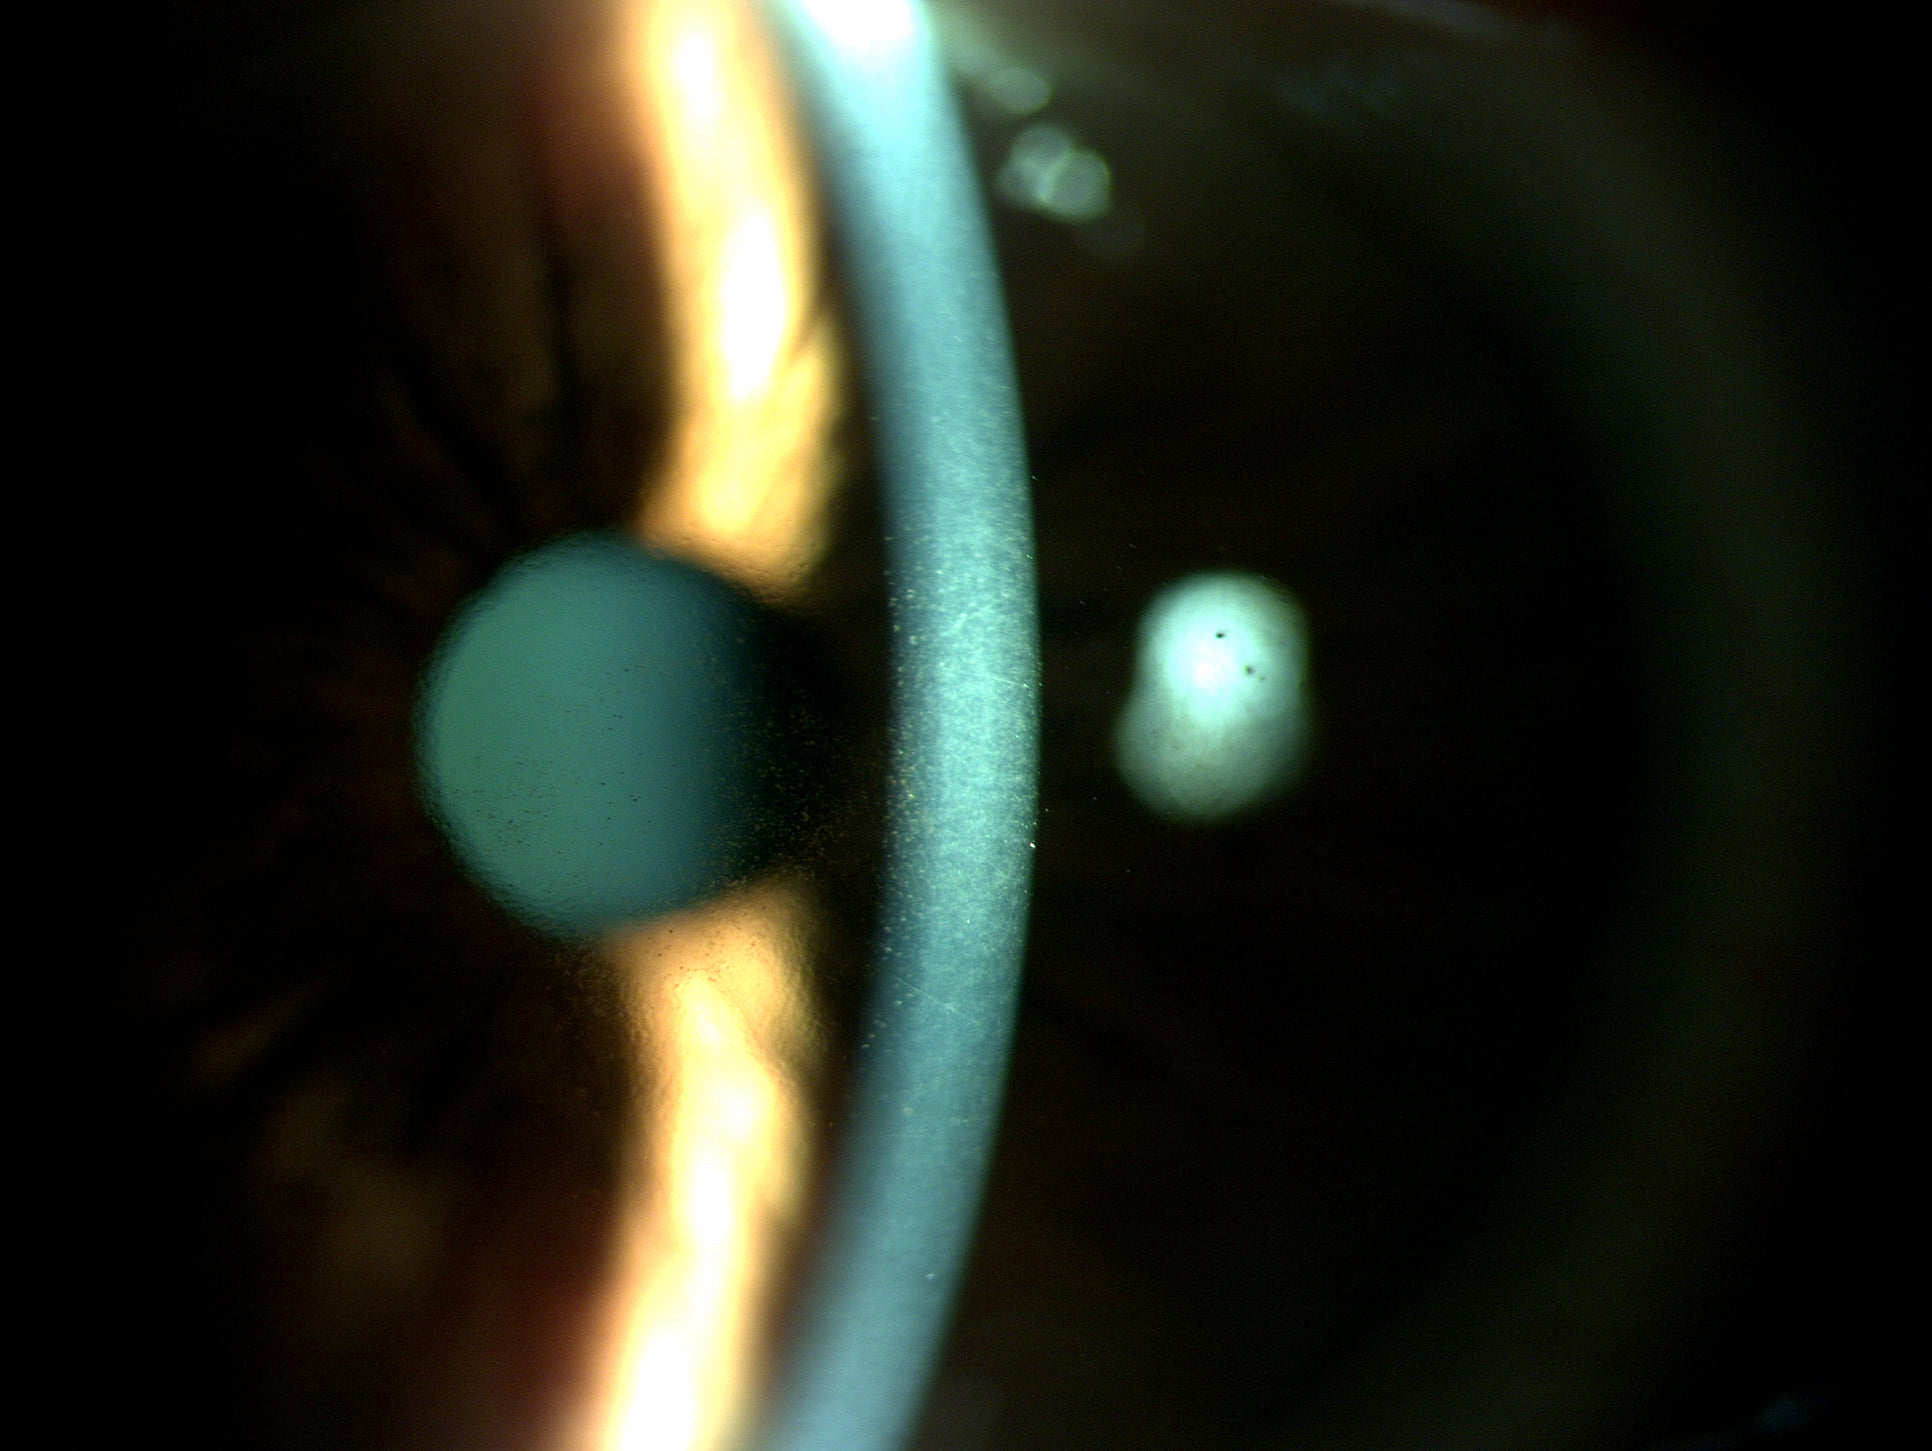

Mai jos, fotografii ale mai multor pacienti de-ai nostri cu Corneea Guttatta în faze medii, sau chiar avansate, la care am efectuat doar operația de cataractă, în urma căreia corneea a „supraviețuit” cu brio și nu a mai fost nevoie – cel puțin până acum – de un trasplant de cornee.